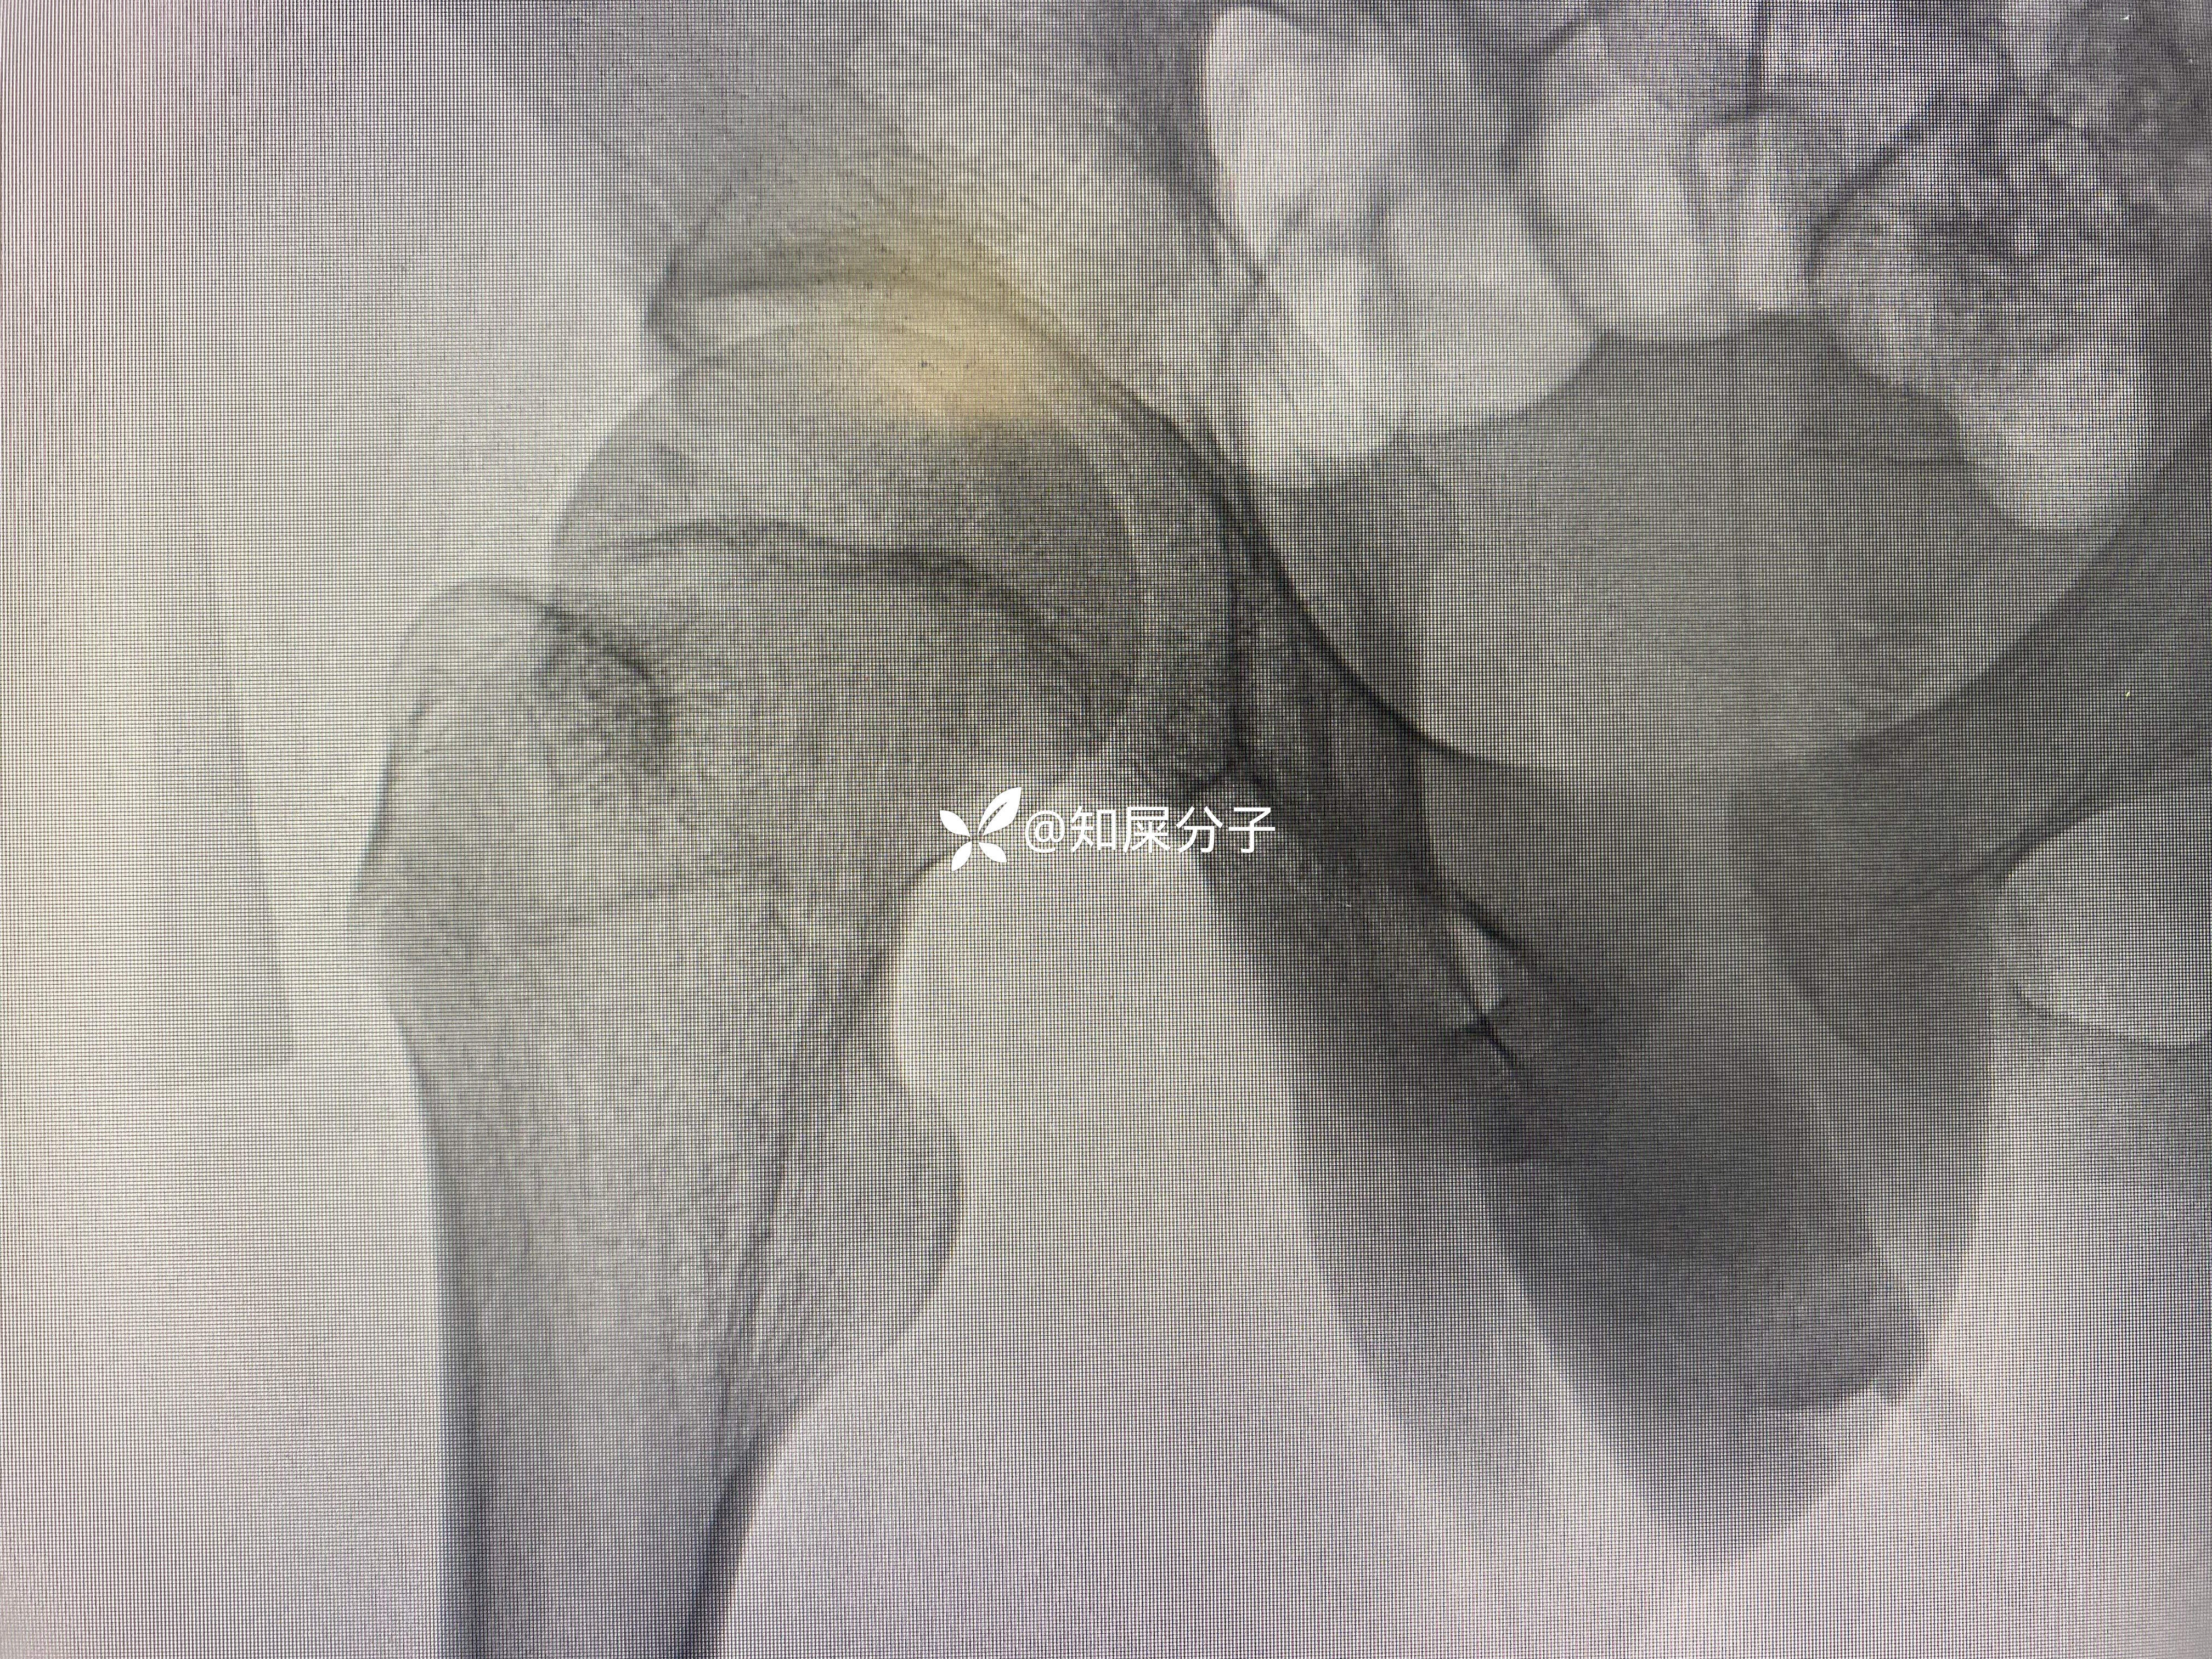

男,17岁

入院检查如下: